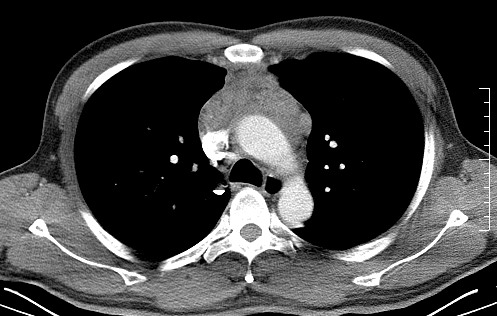

男   40   反复腹痛入院行彩超检查示胸骨右缘4、5肋间不均质回声团

淋巴瘤:前纵隔可见多组肿大的淋巴结,部分融合,有液化坏死

莲蓬籽征  考虑淋巴瘤